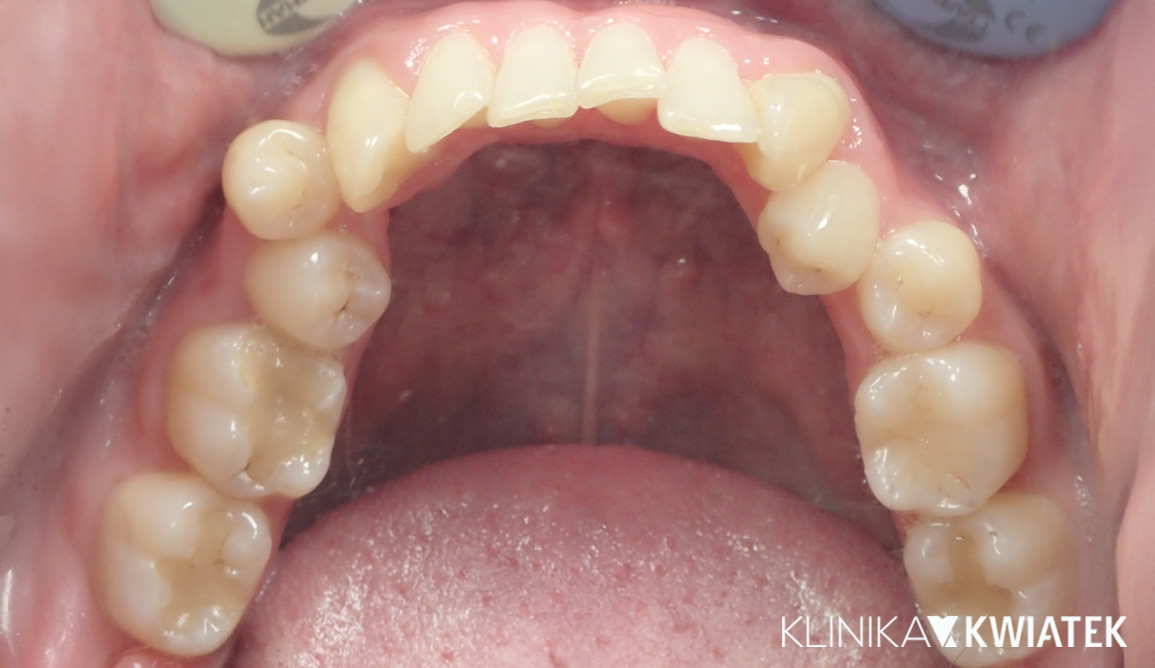

PRZED

PO

Precyzja, plan i efekt - metamorfoza uśmiechu w nowoczesnej stomatologii

Pacjentka zgłosiła się do naszej kliniki z licznymi problemami stomatologicznymi: rozległą próchnicą, koniecznością powtórnego leczenia endodontycznego oraz brakami zębowymi wpływającymi na estetykę i funkcję żucia

Zastosowano kompleksowy, wieloetapowy plan obejmujący higienizację,wybielanie, leczenie zachowawcze, implantologię, ortodoncję oraz protetykę. Efektem jest w pełni funkcjonalny, estetyczny i zdrowy uśmiech Pacjentki.